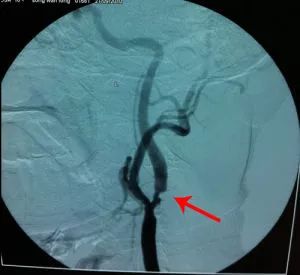

颈动脉狭窄外科治疗包括颈动脉内膜剥脱手术和支架治疗两种。内膜剥脱是在颈部切口,将斑块取出,然后再将血管缝合上,是比较经典的手术方式,不需要吃过多的抗血小板药物,比较彻底,费用也较低,虽然这项技术在国外开展非常普遍,但是国内掌握该项技术的医生相对较少,由于内膜剥脱手术一直称为颈动脉狭窄治疗的金标准,目前国家脑防委也在积极推动颈动脉内膜剥脱手术的开展。现在国内大多数人接受的是颈动脉支架手术,就是把支架覆盖在斑块表面,这种手术方式微创,仅需2mm左右的穿刺切口,多数在局麻下就可完成,目前国内大多数开展介入治疗的单位都能进行治疗,技术也相对比较成熟,但需要口服一些抗血小板的药物,有一定出血的风险,费用相对较高,长期随访的结果再狭窄的发生率稍高于颈动脉内膜剥脱手术。究竟选择哪种手术方式,我认为一是看病人的具体情况,二是看手术者的经验,进行合理的选择,最终的目的是对病人最有利的手术方式,有效的预防脑卒中的发生。